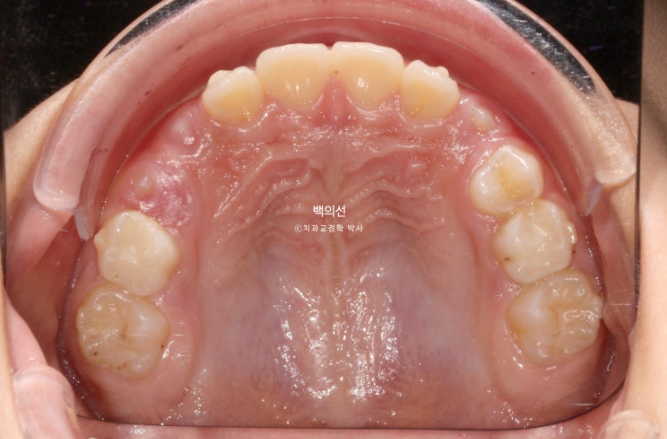

이제 남아있는 유치는 없고 모든 영구치가 제자리에 예쁘게 나왔습니다.

25.07

물샐틈 없는 1급 교합관계를 보입니다.

결과가 성인 2차교정결과에 준하는 만큼 유지장치도 성인교정 유지장치와 동일하게 들어갑니다.

1차 세트 6개월 치료, 9개월간 휴식기, 7개월간 2차세트 치료를 거쳐 마무리된 모습입니다.

23.07~25.07

덧니와 과개교합의 개선입니다.

앞니 돌출의 개선

교합의 개선